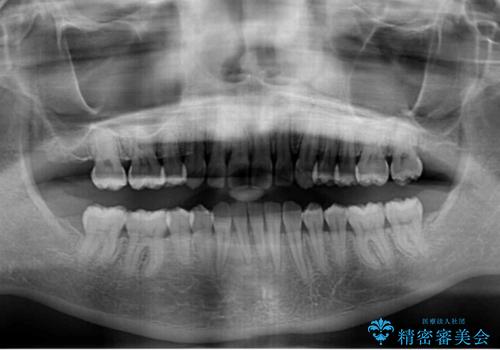

- 八重歯を気にして来院された患者様です。

八重歯の後ろの歯を1歯抜歯し、補助装置(リンガルアーチ)を用いて八重歯の位置を改善し、その後インビザラインにより矯正治療を行うこととしました。

下顎前歯が1本欠損したスリーインサイザーという状態であるため、上下の前歯の咬み込みが深くなったり、奥歯の咬み合わせが理想的なものとならなかったりという仕上がりになってしまいます。

前歯の見た目や奥歯の咬み合わせに、患者様が違和感を感じない状態として治療を終えました。